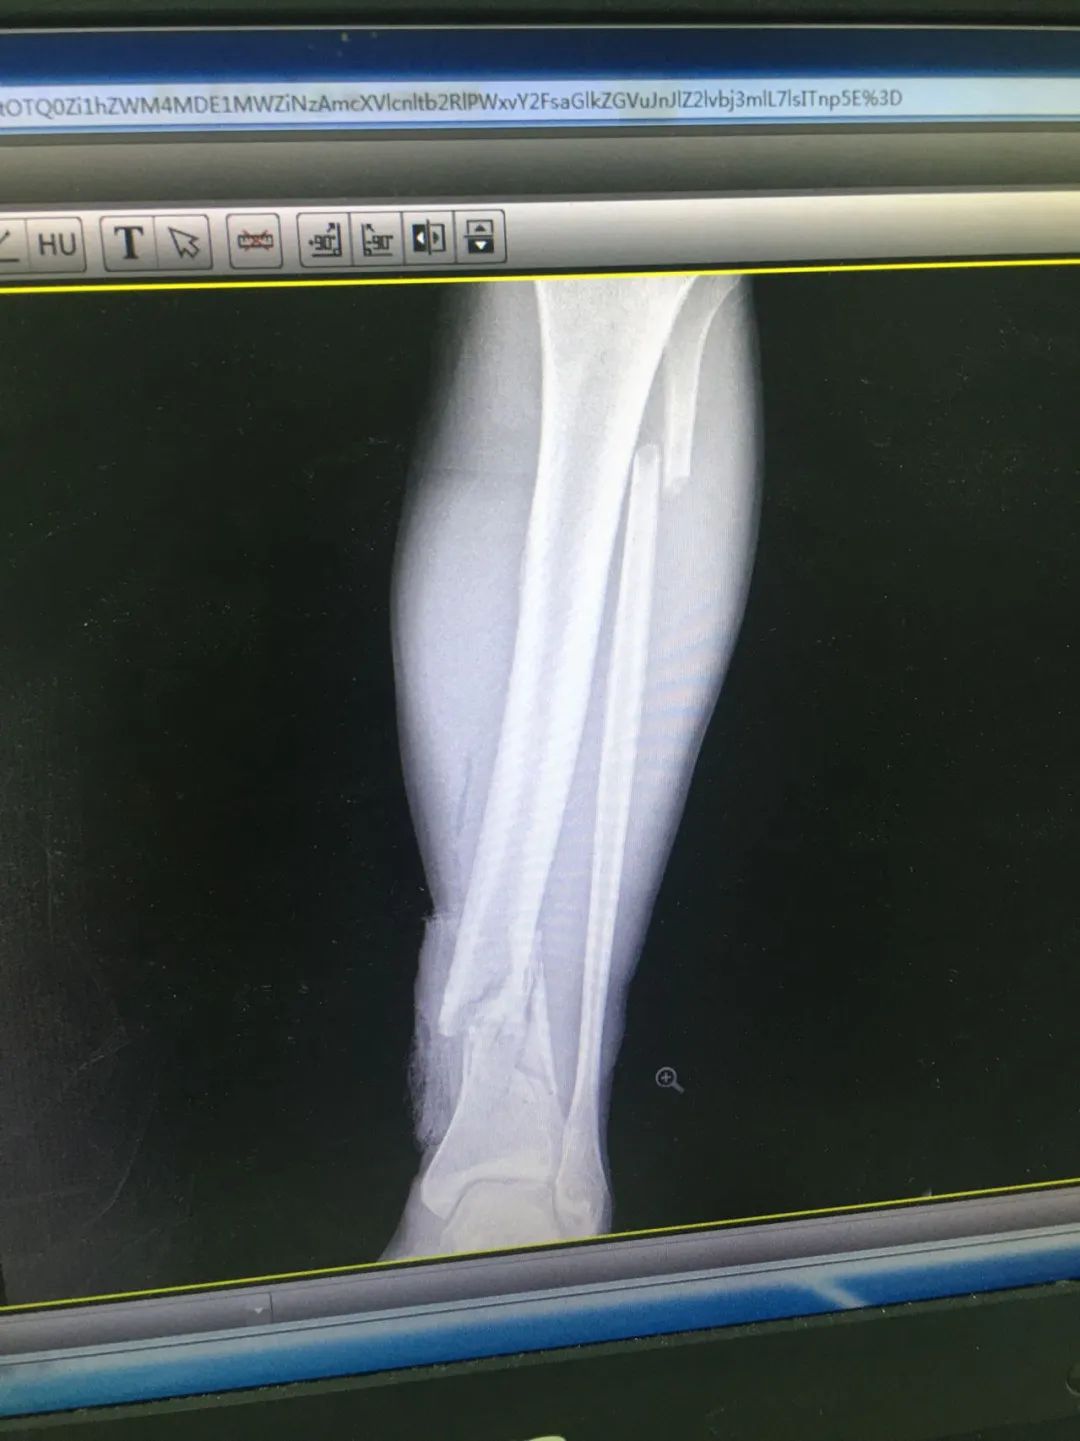

入院時,劉先生已失血性休克。急診科為劉先生安排X線及CT攝片檢查,顯示左股骨干、左腓骨上端骨折,左脛骨遠端粉碎性骨折,頭皮及全身多處皮膚軟組織挫裂傷,隨后收治于骨科。

第1次手術(shù)10天后,骨科為劉先生安排了第2次手術(shù),歷經(jīng)3個小時,成功完成左股骨干骨折及左脛骨遠端骨折閉合復(fù)位內(nèi)固定術(shù),植入兩根30cm×10mm、34cm×10mm髓內(nèi)釘。

術(shù)后一周,患者手術(shù)切口愈合良好,左下肢皮膚感覺及肌力正常,左足末梢循環(huán)恢復(fù),復(fù)查X片顯示骨折復(fù)位標(biāo)準(zhǔn),內(nèi)固定物位置良好。